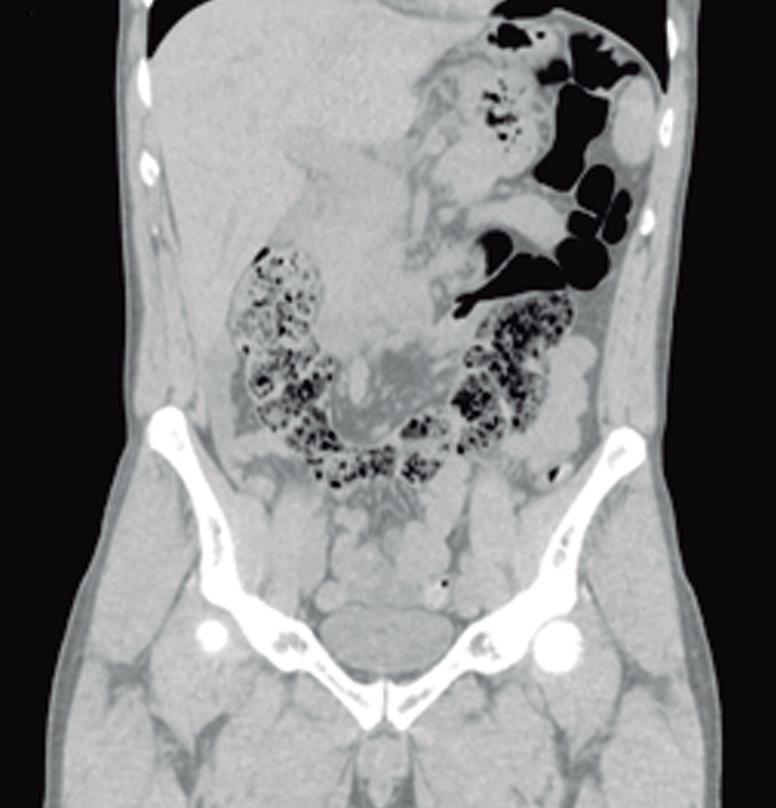

Más allá del diagnóstico de esta anomalía debemos buscar signos imagenológicos indirectos de obstrucción gastrointestinal, como son la dilatación gástrica y de la 1° porción duodenal (Figura 10), con estrechez de la luz del duodeno en el sitio por donde transcurre a través del páncreas anular.18,19

A) Tomografía computada con contraste, plano coronal. El páncreas anular (flecha) provoca dilatación de la 1° porción del duodeno (cabezas de flecha). B) Tomografía computada con contraste, plano axial. Flechas: páncreas anular. Cabeza de flecha: duodeno. C) Tomografía computada con contraste, plano axial, corte más caudal que el previo. Flechas: páncreas anular.

Figura 10. Páncreas anular con obstrucción del tracto de salida gastrointestinal